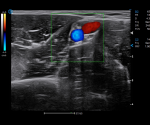

- Category: Color Doppler

Click on images to enlarge

VS Flow is highly sensitive to low velocity blood flow signal and especially suitable for superficial blood flow examination